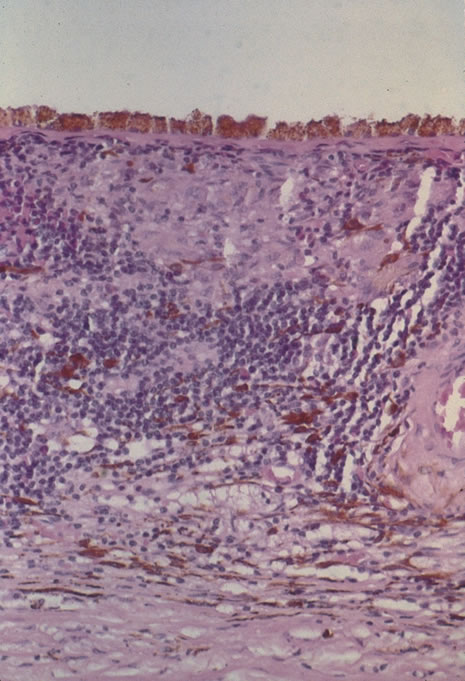

Any cell type may be infected, appearing larger than normal (cytomegalic) and demonstrating eosinophilic intranuclear “owl's eye” and smaller intracytoplasmic viral inclusion bodies, which are better seen with Giemsa or Papanicolaou's stains (Fig. 8). Histologic examination of tissue specimens, including bronchoalveolar lavage fluid and urine, may be useful for diagnosis.

Fig. 8. Typical lesion of cytomegalovirus (CMV) produces retinal necrosis with large cells possessing owl's eye inclusions.